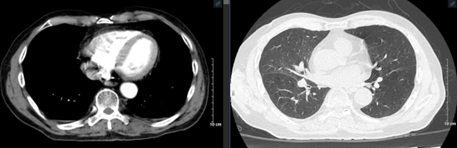

Chụp cắt lớp vi tính lồng ngực: Thùy dưới phổi trái có khối tỷ trọng tổ chức kích thước 30x21mm sau tiêm ngấm thuốc, thượng đòn phải và trung thất có vài hạch, nhóm 2, 4 lớn nhất kích thước 16x17mm, bờ rõ, ngấm thuốc sau tiêm.

Hình 1: Hình ảnh cắt lớp vi tính lồng ngực: Phổi trái có khối tỷ trọng tổ chức kích thước 30x21mm sau tiêm ngấm thuốc (vòng trong màu đỏ)

Chụp cắt lớp vi tính ổ bụng: Dọc động mạch chủ có vài hạch, lớn nhất kích thước 11x8mm, bờ rõ, ngấm thuốc sau tiêm. Tuyến thượng thận trái dày thân tuyến 12mm, không tạo nốt khu trú.

Hình ảnh chụp cắt lớp vi tính lồng ngực sau 3 chu kỳ điều trị hóa chất:

Trước điều trị

Sau điều trị

Hình 3: Hình ảnh chụp cắt lớp vi tính lồng ngực trước và sau điều trị

Nhận xét: Trước điều trị hóa chất thùy dưới phổi trái có khối tỷ trọng ngấm thuốc, thượng đòn phải và trung thất có vài hạch, nhóm 2, 4 bờ rõ, ngấm thuốc sau tiêm, các hạch dọc động mạch chủ bụng ngấm thuốc, tuyến thượng thận trái dày thân tuyến, tuy nhiên sau điều trị hóa chất 3 chu kỳ, không thấy hình ảnh khối tỷ trọng ở phổi, các hạch ở trung thất, thượng đòn, dọc động mạch chủ bụng cũng như hình ảnh dày thận tuyến thượng thận.